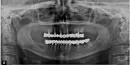

Месяц назад сделали протезирование моих зубов металлокерамической конструкцией. И верхние и нижние конструкции единые. До сих пор я чувствую дискомфорт и боли, тем более когда ем (даже мягкую пищу, например хлеб). Врач успокаивает, что со временем все пройдет, просто надо терпеть, что все сделано правильно. Я бы очень хотела узнать Ваше профессиональное мнение по поводу конструкции и протезирования моих зубов, узнать, действительно, со временем боли пройдут? Для этого я Вам отправляю панорамный снимок, который сделала вчера.

Ваш стоматолог, как минимум, мало понимает в протезировании. Справа от меня (2-ой сегмент) вообще все три корня необходимо удалить, все это вывалится. Слева в зубе на верхушках воспаления, и вообще все сделано неграмотно.